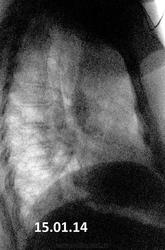

А, ксати, что это за треугольник на боковой?

Приложения:

1966g.r.15.01.2014_prav.bok_.jpg

Скиалогия мягких тканей, как вариант.

Треугольник-мышца.